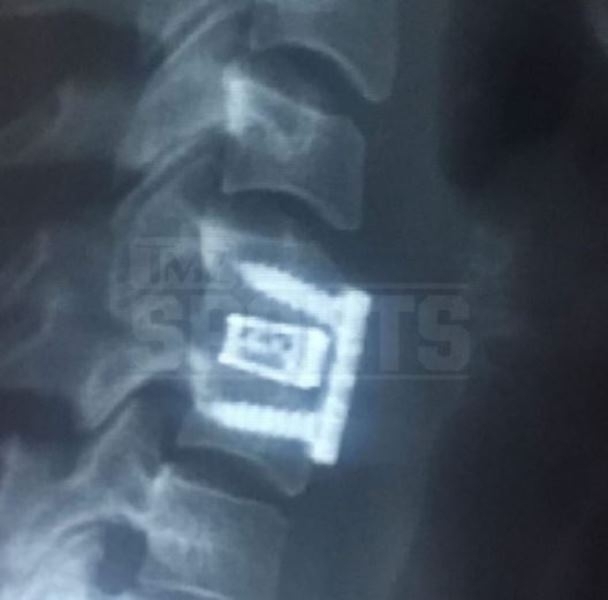

Фронтц утверждает, что ей потребовалось хирургическое вмешательство — в шею вживили титановую пластину, которая держится на 4 винтах. Дама поделилась фотографиями с корреспондентами TMZ Sports. Фронтц делится воспоминаниями: «Он ударил меня в лицо. Нос словно взорвался. Кровь была повсюду, по всей квартире. На стенах, на полу. Везде...»